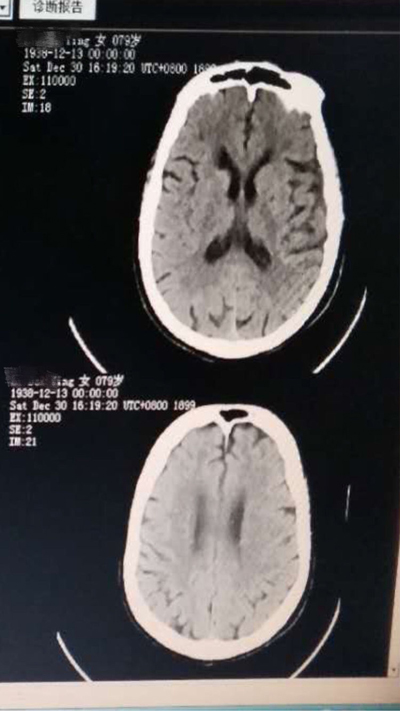

病例二:第一例脑梗死行阿替普酶溶栓治疗

患者何某某,男,53岁,归义镇人,因言语不清1小时,于2018年1月29日入院,患者有高血压病史,控制欠佳。体查:神清,言语含糊,口角不斜,伸舌居中,四肢肌力正常,病理呈阴性,NIHSS评分2分,考虑急性脑梗死可能性大。

溶栓前头颅CT,排除脑出血

患者无静脉溶栓禁忌症,告知家属溶栓风险,家属同意,立即启动阿替普酶静脉溶栓,约24小时左右症状明显缓解,语言清晰,无明显后遗症,NIHSS评分0分。

第二天复查头颅核磁:右侧额顶叶交界处少许急性脑梗死病灶,颅内血管未见异常。